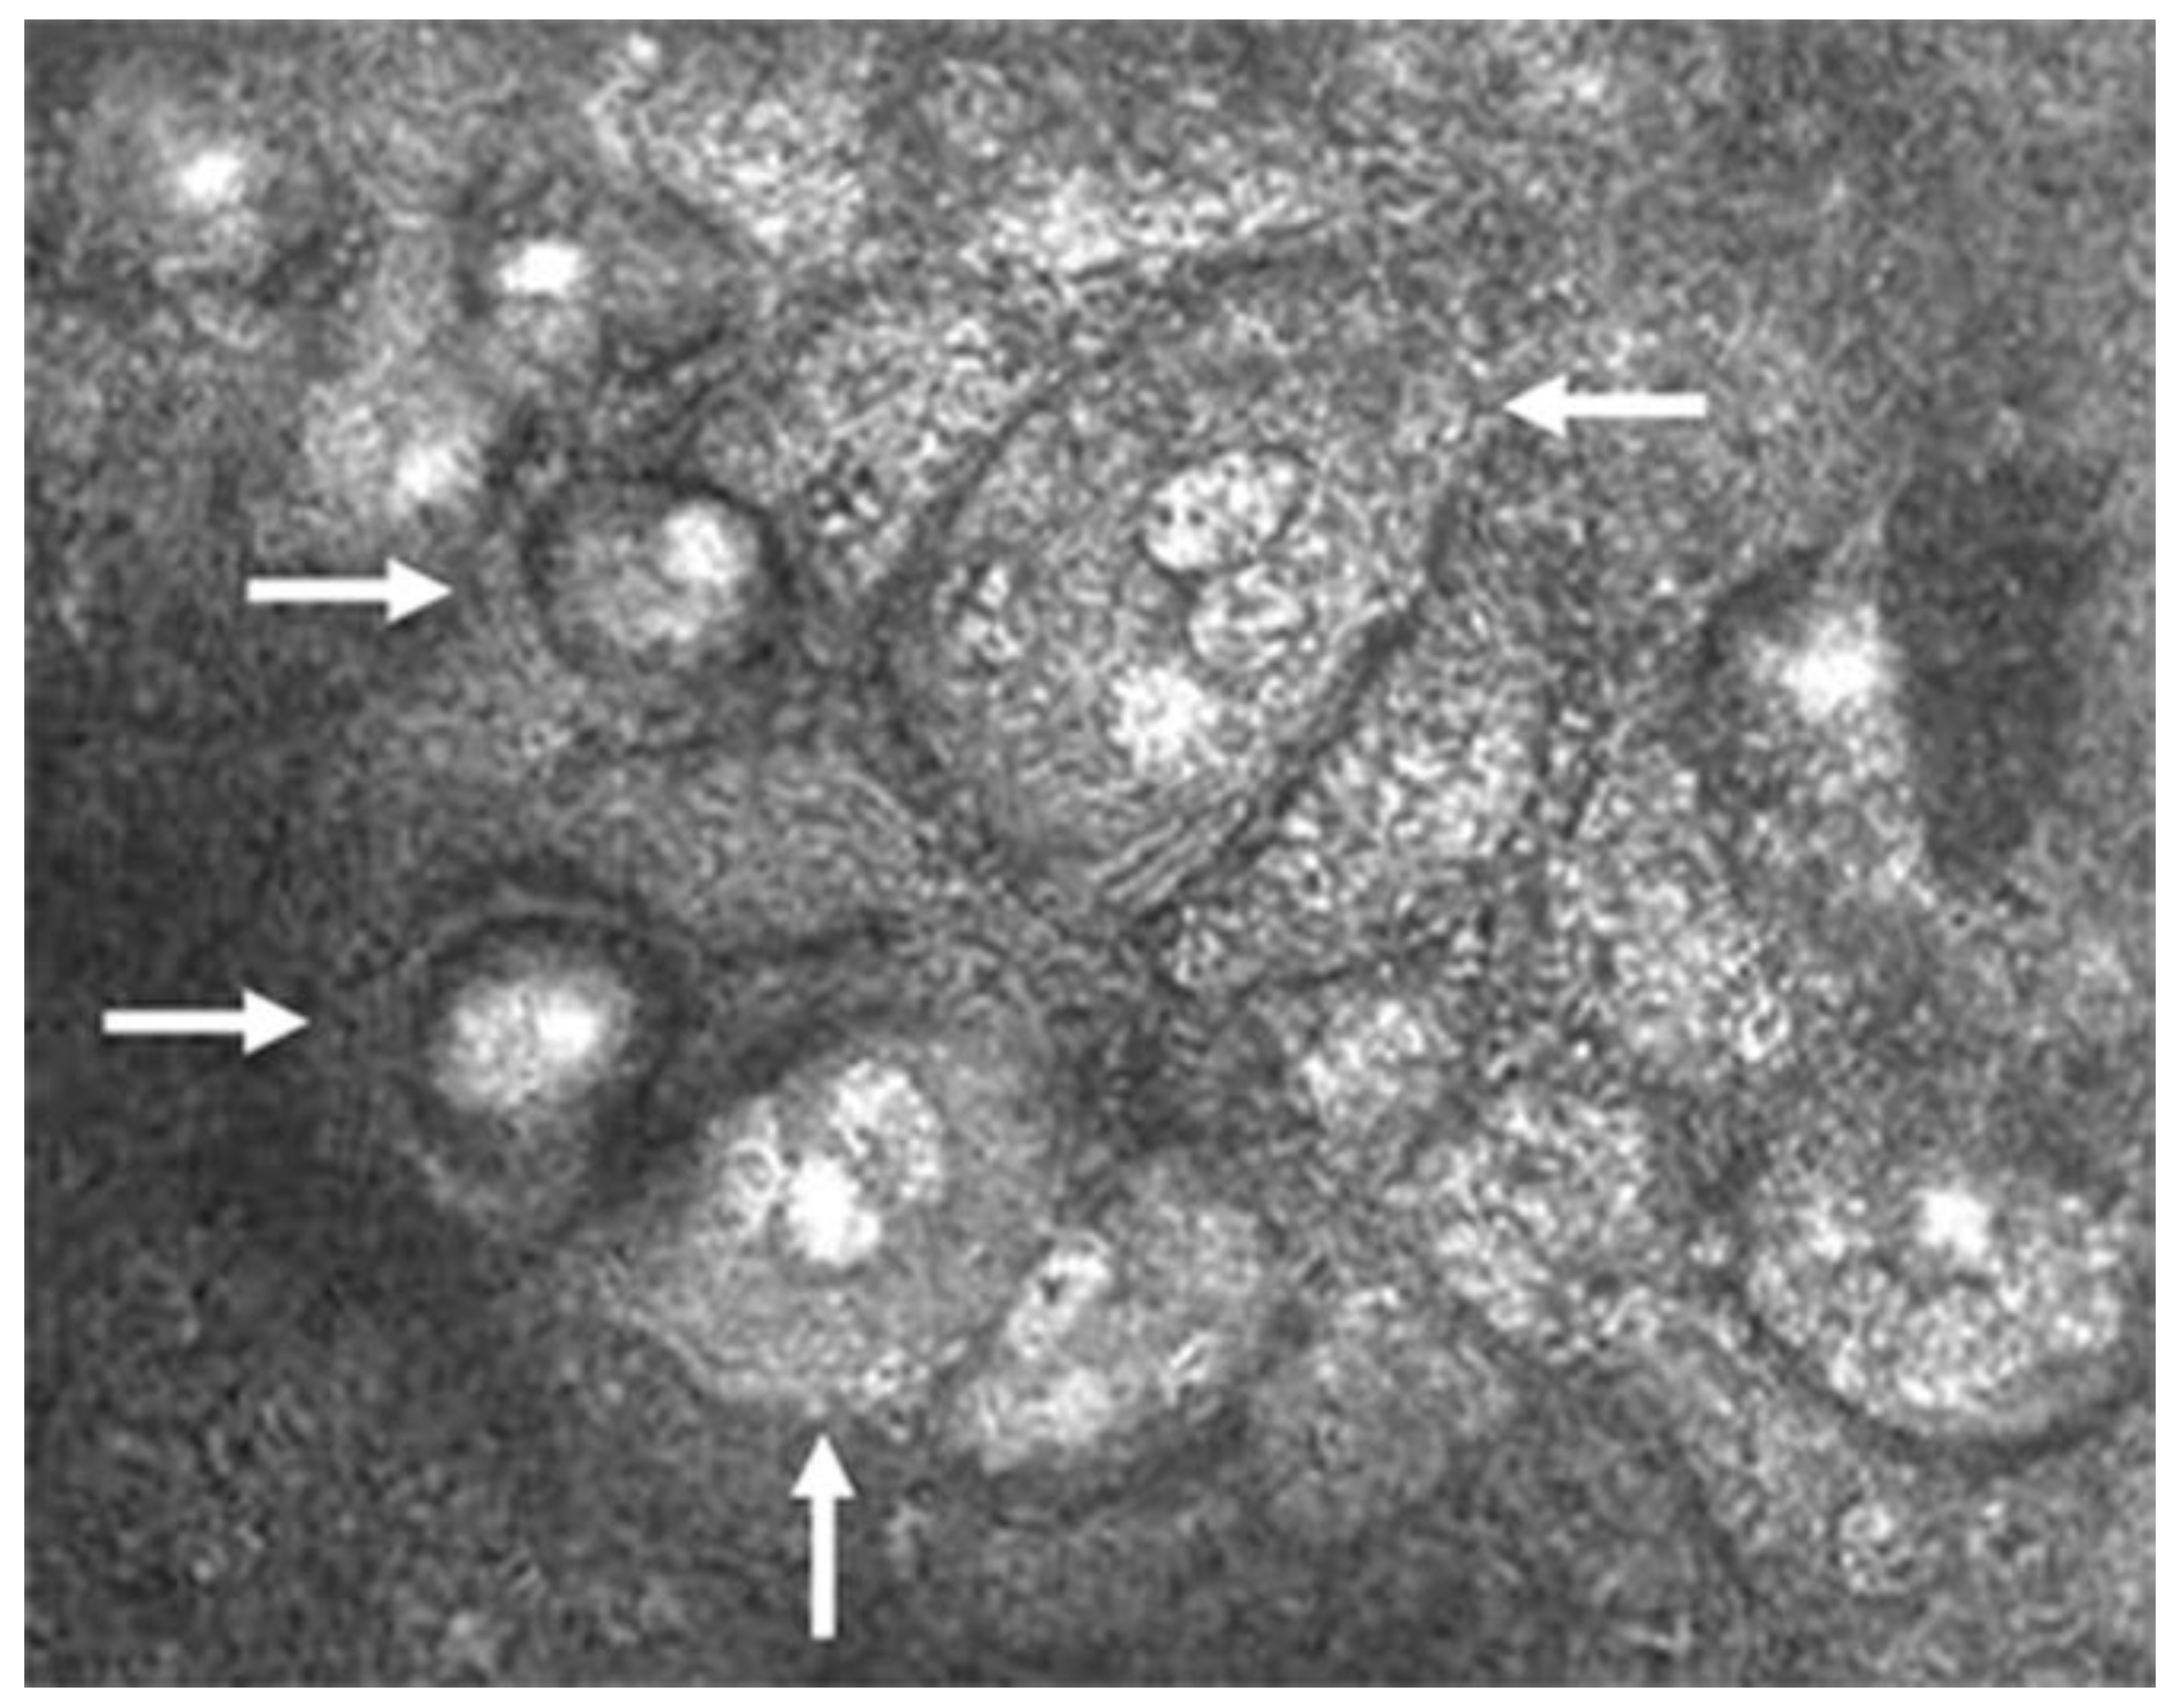

The pathognomonic finding confirming the diagnosis of CMV is the presence of inclusion bodies and macrophages on confocal microscopy (“owl’s eye”; Figure 4) [2,33,40]. This finding is specific to CMV and is not seen in HSV, VZV, or other viral entities. Finally, anterior segment spectral-domain OCT can show high reflectivity of posterior corneal lesions, which are presumed KPs, but unlike the finding of “owl’s eyes” on confocal microscopy, this finding is not specific to CMV [41].

Figure 4.

Confocal microscopic image of CMV endotheliitis at the level of corneal endothelium showing a group of large cells whose nuclei have a high reflection area surrounded by a halo of low reflection, resembling an “owl’s eye” as represented by white arrows (Courtesy of Shiraishi et al.; used with the permission of the publisher [44]).